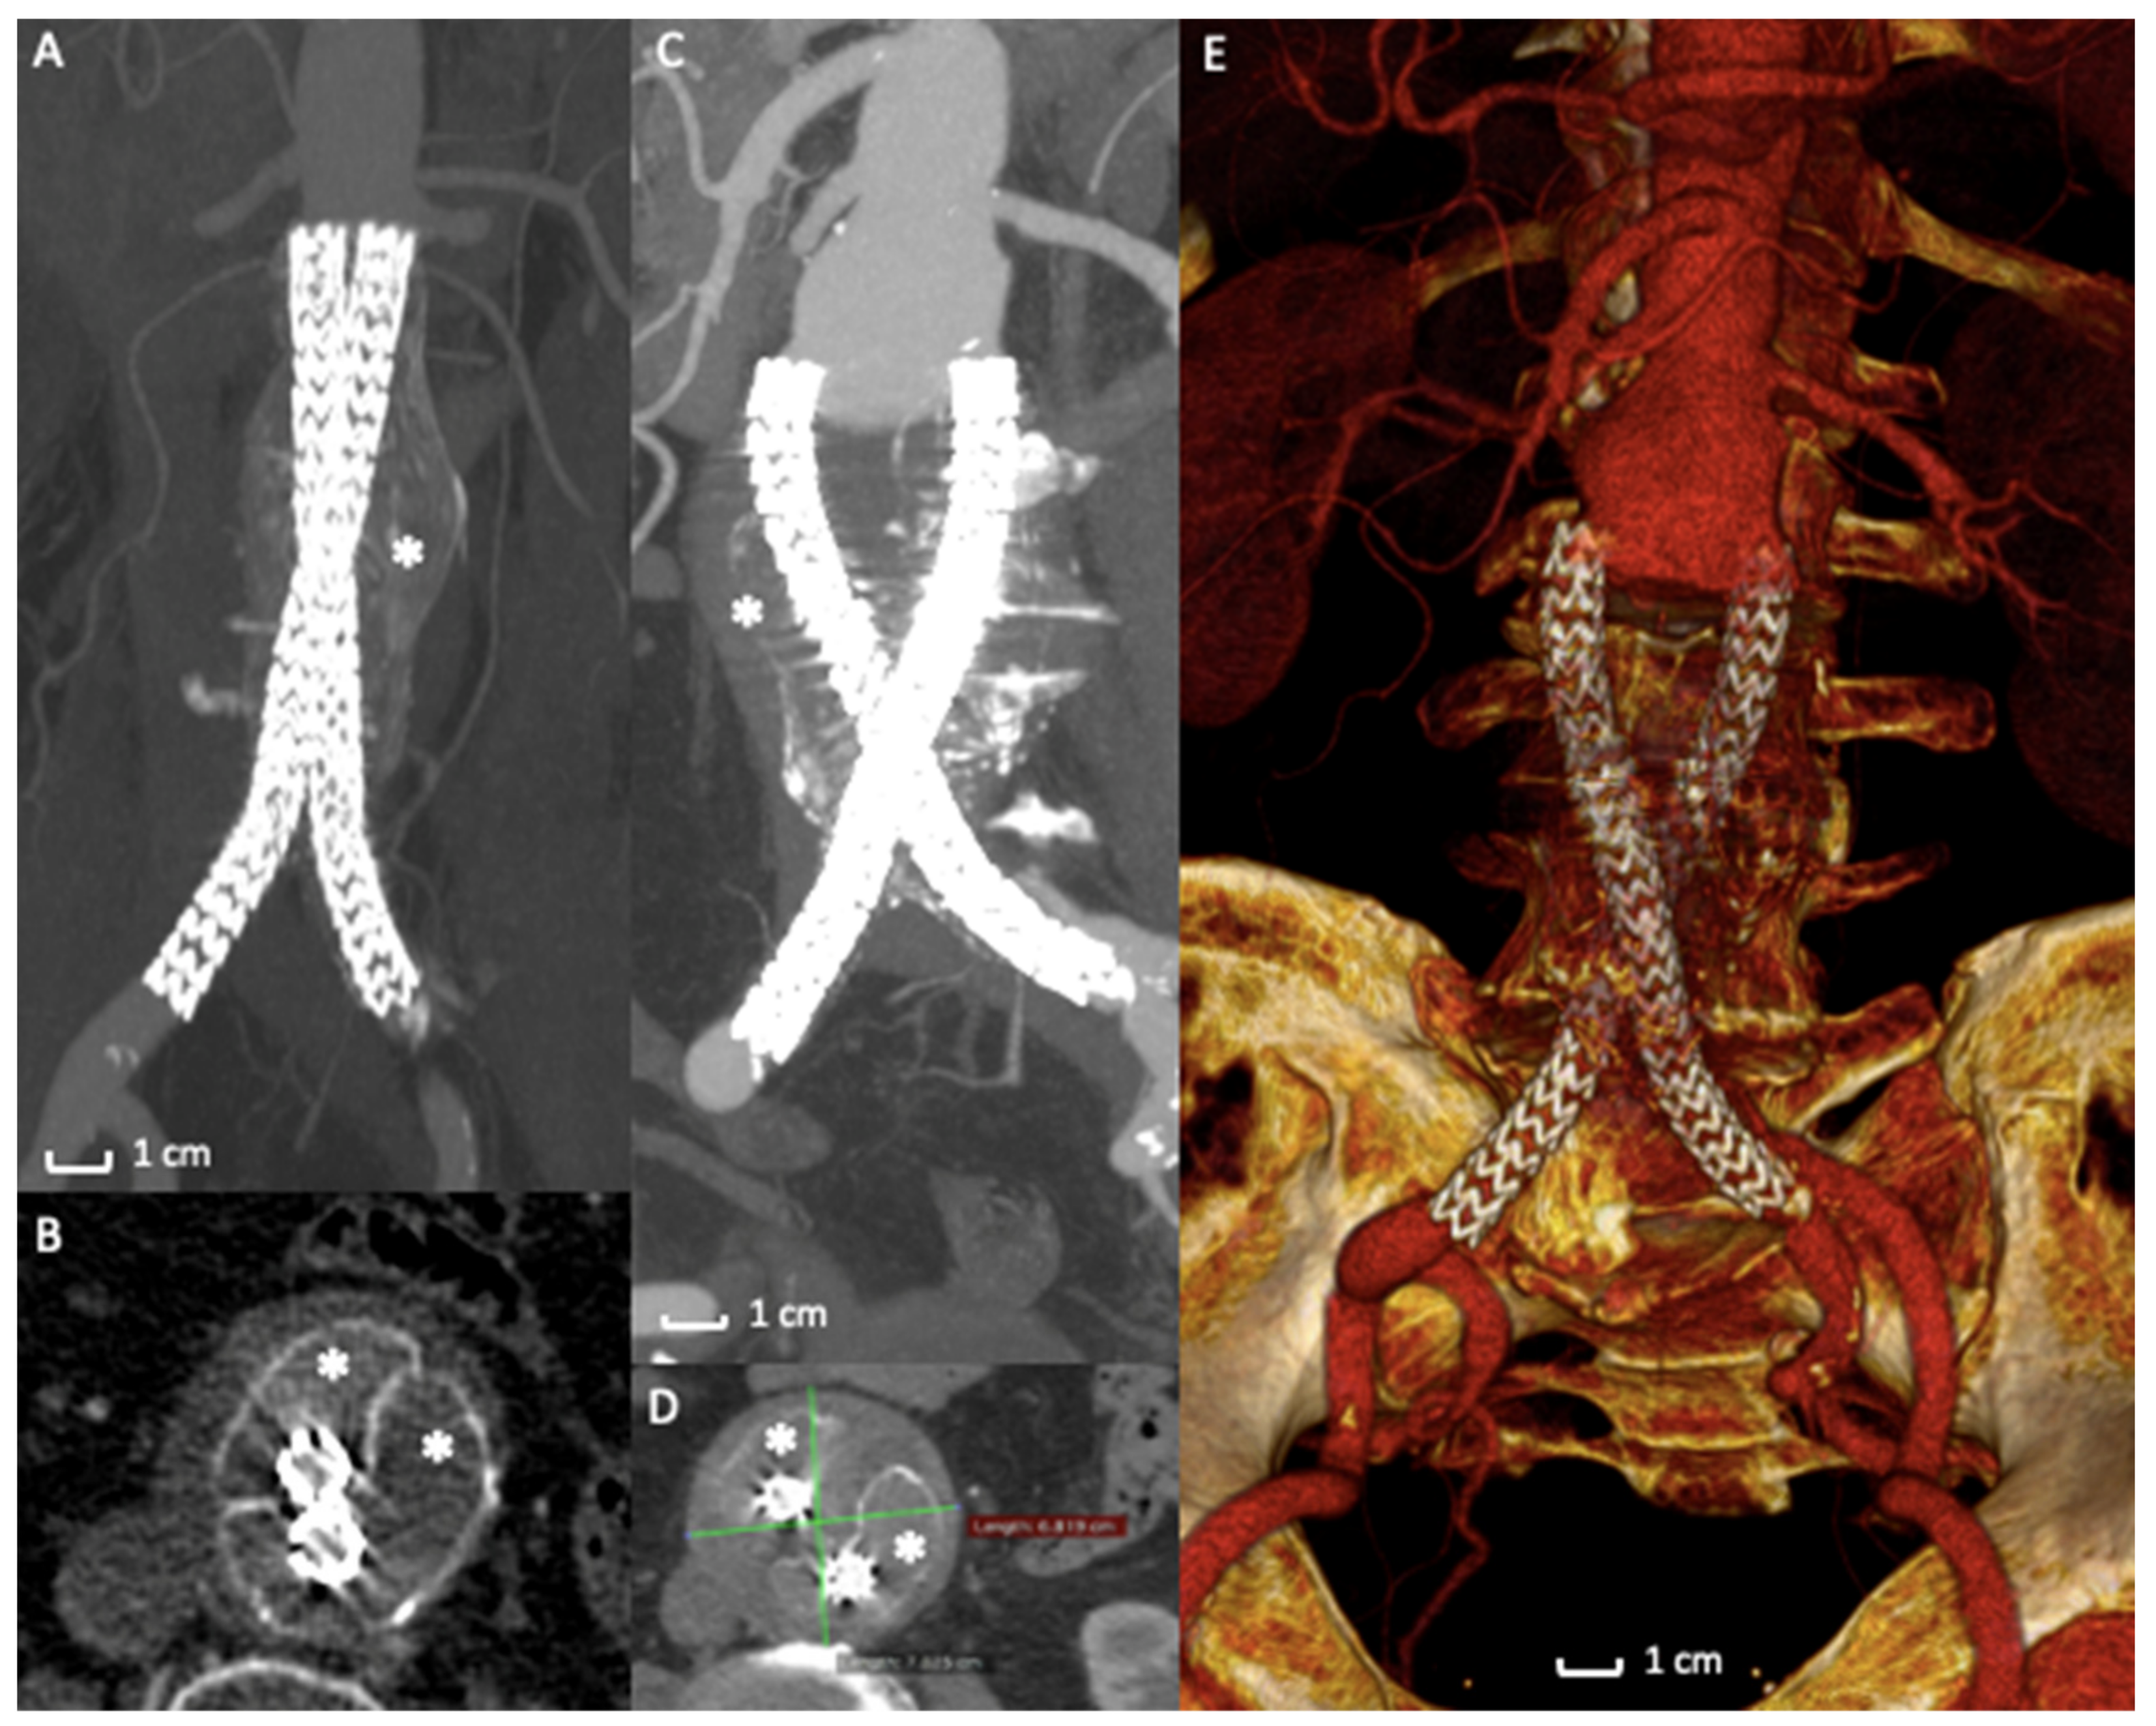

In a retrospective analysis [66] of prospectively collected data of 295 cases of endovascular aneurysm sealing using the Nellix device for abdominal aortic aneurysm, therapeutic failure was seen at a surprising and alarming rate of 33.2%. The most common failure mechanism was the stent graft migration associated with type IA endoleak and sac expansion, as demonstrated by a recent systematic review (Figure 4A–E) [58]. In several cases of failure, stent grafts were explanted from the patients’ bodies with a significant open vascular intervention. EVAS failures were also responsible for AAA rupture with severe or fatal consequences for the patients. In case of graft explantation, surgeons noted that the bags containing polymer were still intact, the polymer was not leaking into the vasculature, and maintained the expected consistency. The cause of failure was reported to be the lack of a stable proximal fixation of the entire device into the aneurysm sac [67,68,69].

Figure 4. Case of Nellix Endograft Failure due to distal migration. (A) Computed Tomography Angiography detail of a Nellix endograft implantation. The asterisk (*) indicates the polymer filled endobags that correctly seal the aneurysm sac. (B) Axial view of the same exam highlights the correct stents’ and endobags’ configuration, asterisks (*) mark the two endobags adapted to the aneurysm sac. (C) Computed Tomography Angiography detail of the 2-year follow-up exam revealing a distal migration of the entire system (arrows) with AAA enlargement (D) and endobags dislocation (*). (E) 3D volume rendering of Computed Tomography Angiography of the endograft migration and failure, requiring open surgical conversion.